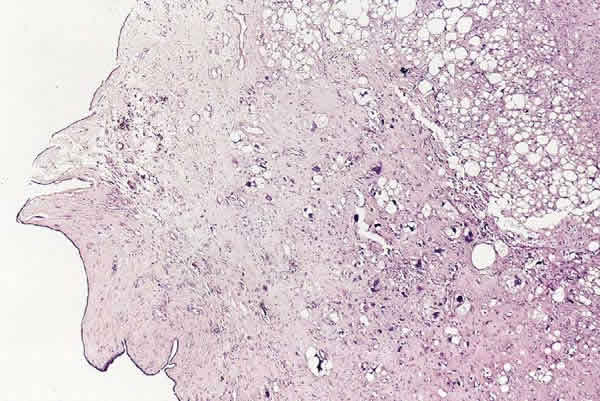

Fig. 7: Tumor filodes maligno de mama. Distintos patrones mesenquimales. HE. 10x.